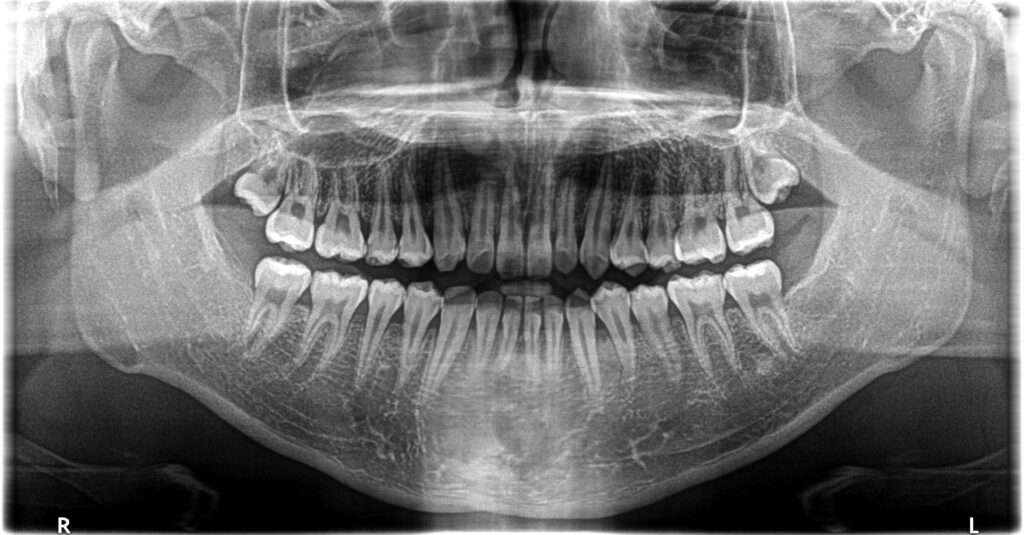

- 診断:1級咬合、左偏位、下永久歯(犬歯)萌出スペース不足

- 治療方針:非抜歯で行う。虫歯予防(フッ素)、歯磨き指導、舌位の改善、上下拡大床+補助断線→マウスピース矯正→下親知らずの抜歯、保定→メンテナンス

13歳頃、永久歯列になったところで、1期治療終了。後は親御さんが希望されたため、メンテナンスに移行し、高校生になったら下の親知らずを抜歯することにしました。

高校2年生で下の左右の埋伏の親知らずを抜歯しました。下の埋伏親知らずは、将来の歯並びの予後に悪い影響を与えたり、年齢が上がるにつれて抜きにくくなるので、できれば早期の抜歯が望ましいと考えています。一方、上の親知らずのは抜歯は簡単なことが多く、手前の7番や開咬などの不正咬合に悪い影響をあたえなければ、下程急ぐ必要はないかもしれません。当医院では一応下の親知らずの抜歯をもって、ある程度の矯正は終了と捉えています。しかし、管理されるのが嫌、抜きたくない方、他(高次機関等)で抜歯したいという方は13歳位で1期治療は終了という方針です。